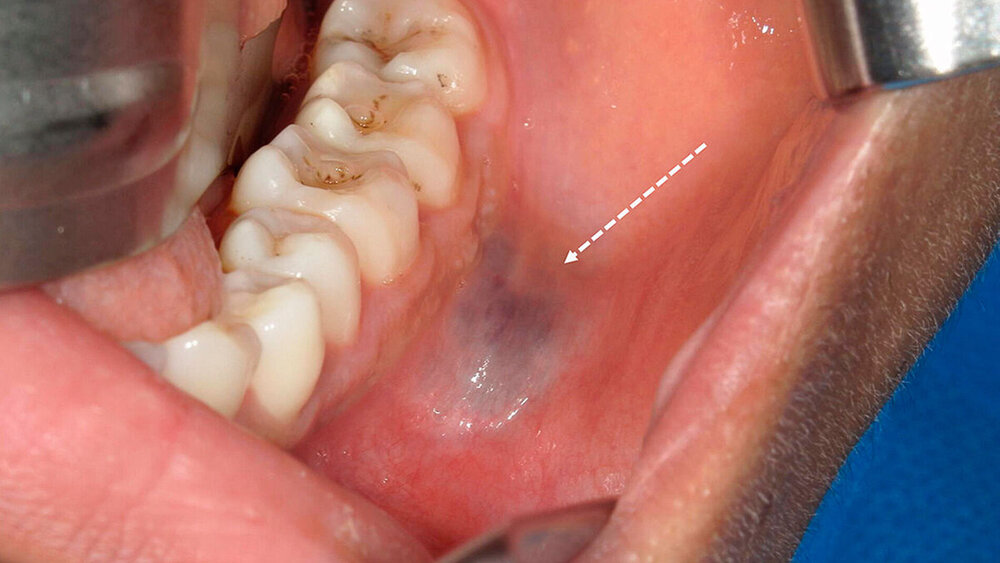

Kopf- und Halskrebsarten umfassen verschiedene bösartige Tumoren, die in Bereichen wie dem Mund, dem Rachen, dem Kehlkopf, der Nase, den Nasennebenhöhlen und den Speicheldrüsen auftreten. Ein wichtiger Risikofaktor ist der Konsum von Tabak und Alkohol, die das Risiko dieser Krebsarten deutlich erhöhen. Auch Infektionen mit dem Humanen Papillomavirus (HPV) spielen bei bestimmten Krebsarten eine wachsende Rolle. Die Fünfjahresüberlebensrate von Kopf- und Halskrebserkrankungen liegt zwischen 40 und 70 Prozent, wobei verschiedene Subtypen unterschiedliche Prognosen aufweisen.